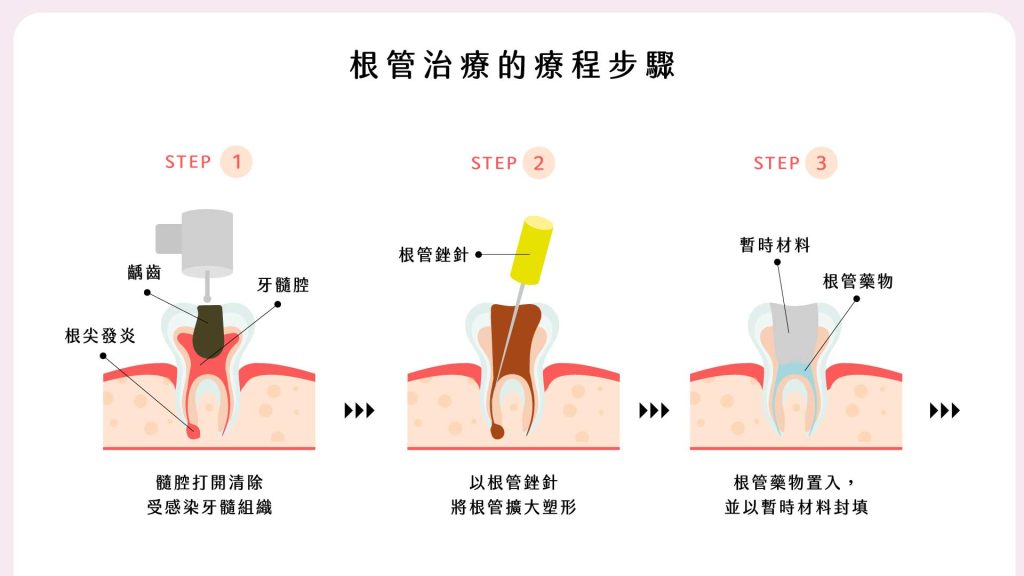

您可能沒聽過根管治療,但一定聽過「抽神經」,其實它們是相同的治療。當細菌感染牙齒內部的牙髓腔,健康神經失去活性,就需要將感染部位清理乾淨,再進行重建修復。

移除牙髓腔裡運輸養分的組織和神經後,養分和水分消失,且療程後可能殘餘少量組織,在自然分解時產生色素並被牙齒吸收,導致牙齒永久變色,隨著時間推移會變成較深的黃、棕或灰色。

根管治療移除較多自然齒質,術後牙齒較脆弱,日後發生磨損、斷裂或崩壞的機率也增加,因此牙拜醫師建議使用牙套保護;另外根管治療屬於「內因性染色」,即色素沉積在牙齒內部,和「外因性染色」相反,因此無法透過外部美白來改善牙色,而同時能保護牙齒與美白的就是「全瓷冠」了。